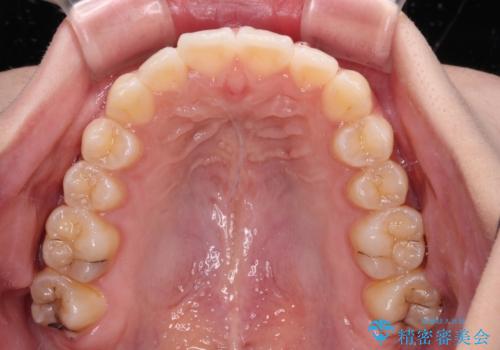

上下前歯の突出感とデコボコを気にして来院された患者様です。

インビザラインによる上下歯列の側方拡大と後方移動、必要に応じてIPR(歯と歯の間を削る)によりスペースの獲得により歯列を整えることとしました。

治療途中、出産や転居があり、2年ほど治療期間が長くなってしまいましたが、前歯の歯並びや飛び出した感覚を無事に改善させることができました。